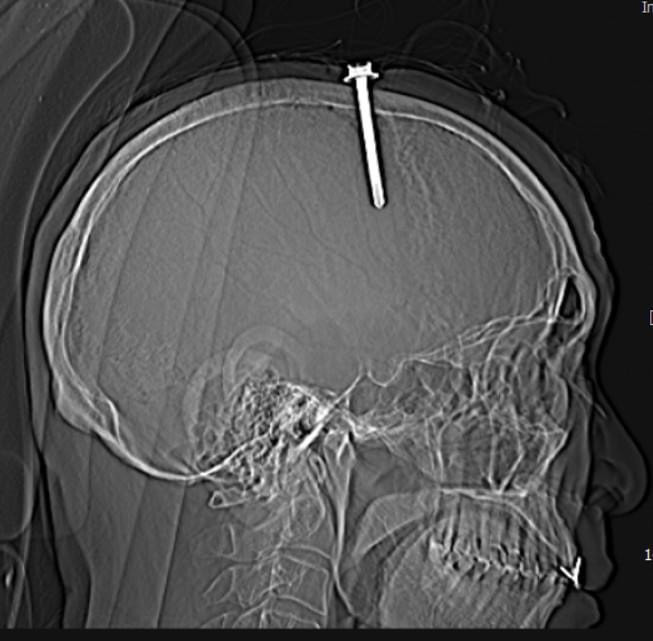

Qua thăm khám lâm sàng và kết quả chụp cắt lớp vi tính sọ não cho thấy bệnh nhân có vết thương sọ não, vết thương xoang tĩnh mạch dọc trên do dị vật kim loại cắm vào vùng đỉnh bên trái, cạnh xoang tĩnh mạch dọc trên. Dị vật có đường kính 0.5 cm, chiều dài 5,1cm.

![]() |

| Vị trí dị vật đâm xuyên |